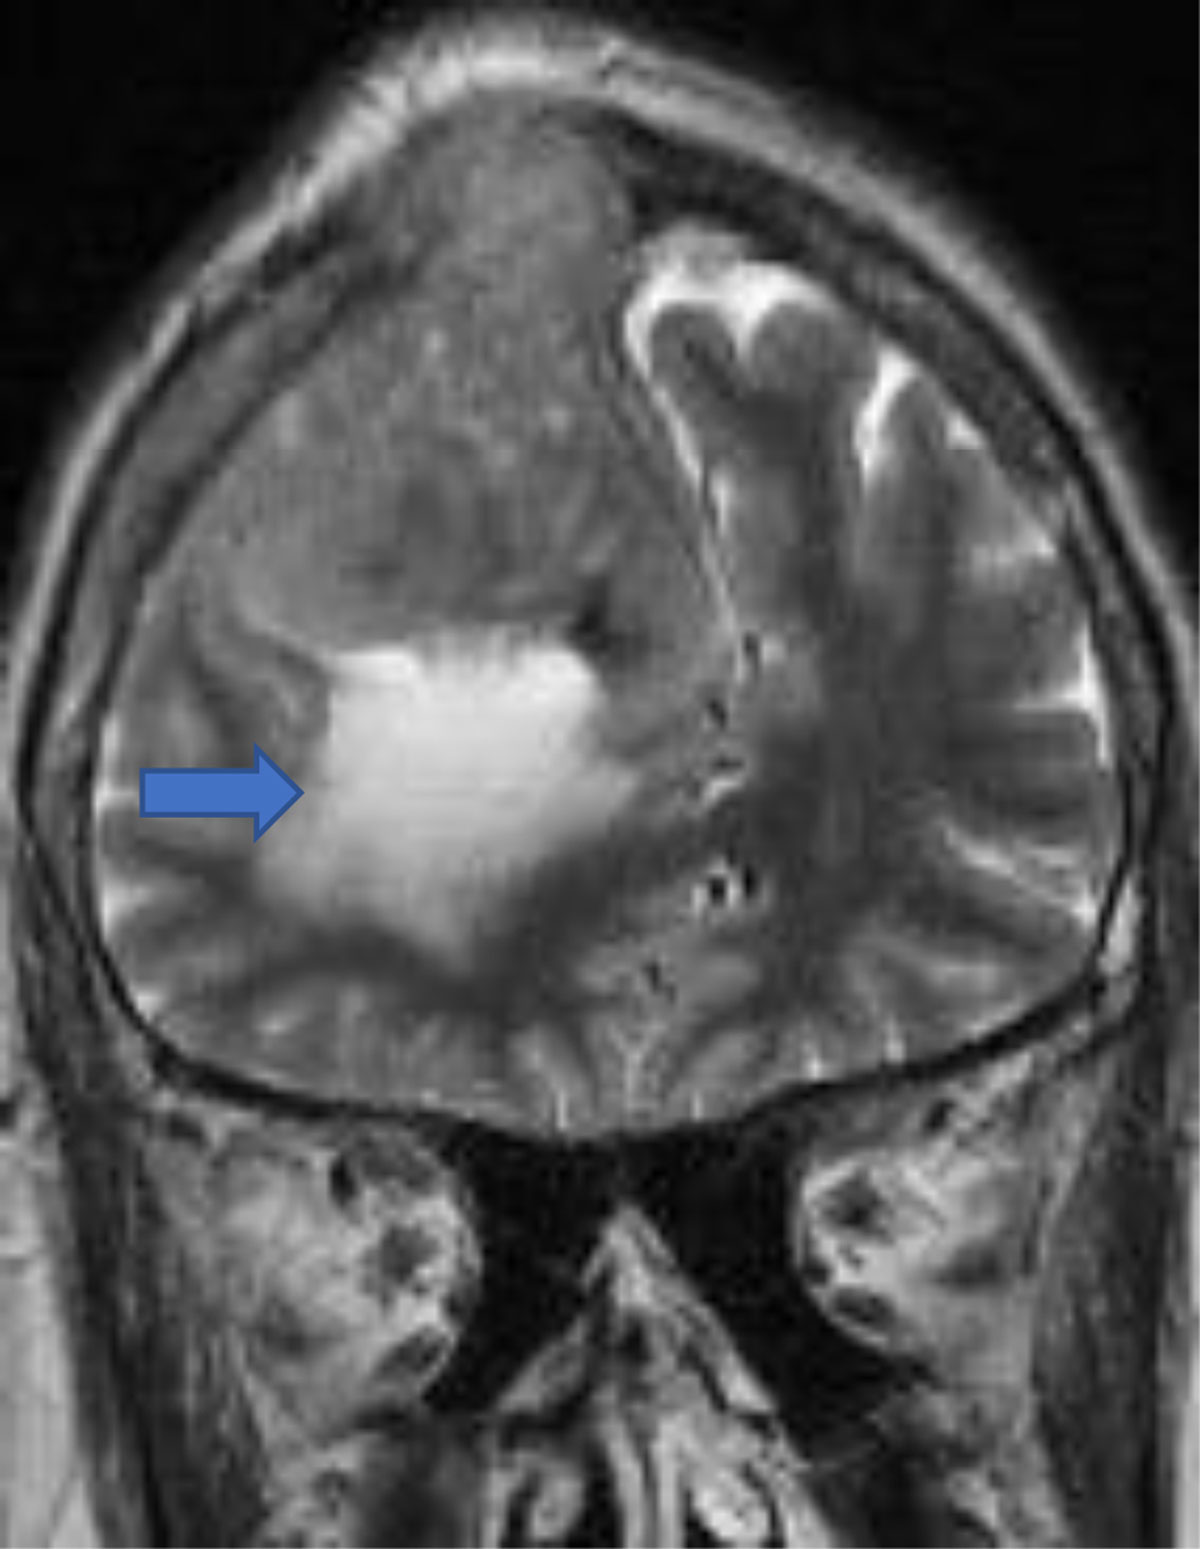

Figure 9

Convexity meningioma with peritumoral edema and (arrow) osseus invasion.

Figure 10

Sagittal post-contrast convexity meningioma with osseous invasion (arrow).